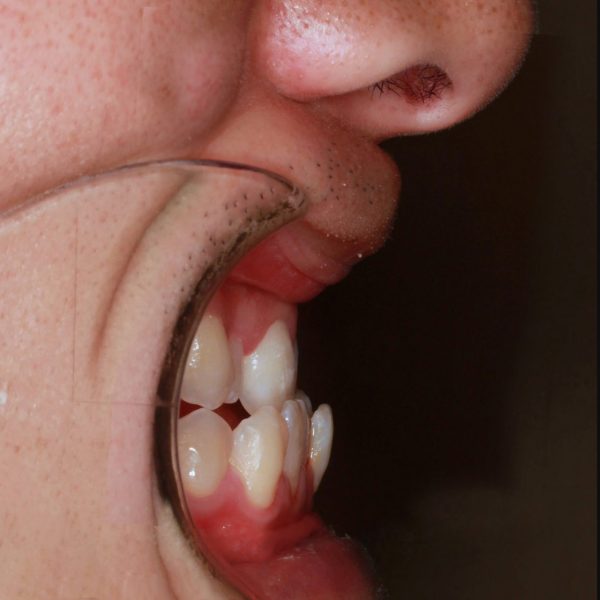

16歳 男性「受け口を治したい」( 反対咬合 )

16歳の男性です。

「受け口を治したい」との事で来院されました。

上下の前歯が逆になっています。右上の犬歯は八重歯の状態です。

叢生を伴う 反対咬合(受け口)です。

小さい頃から受け口だったそうです。

反対の歯ならびが、 お顔の印象に良くない影響を与えています。

お母さん ご本人ともにずっと気にされていたそうですが、今回思い切って 来院されました。

ご本人にとって 口もとが 大きな コンプレックスになっていたそうです。

受け口の治療としては遅い開始時期です。

このため、骨格的な不正も認められます。